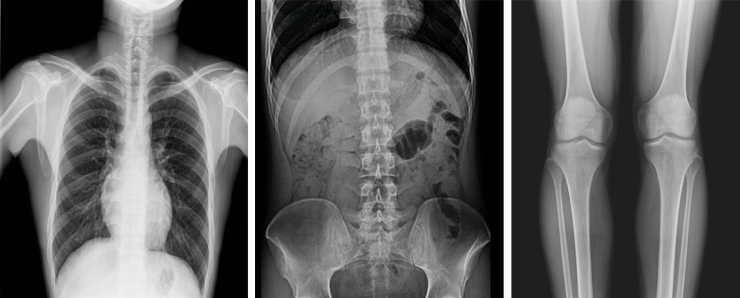

不同于常規(guī)靜態(tài)DR只能進(jìn)行平片攝影檢查,動(dòng)態(tài)DR可以滿足多種臨床檢查需求,包括靜態(tài)檢查、透視檢查、造影檢查、脊柱及下肢全長(zhǎng)拼接檢查,相較于靜態(tài)DR具有豐富的臨床應(yīng)用,且動(dòng)態(tài)DR檢查更精準(zhǔn)、直觀,擺位攝片效率極大地提升,大大節(jié)省拍片時(shí)間。

更多高級(jí)智能應(yīng)用

動(dòng)態(tài)DR影像采集幅面大,17×17英寸超大視野,可覆蓋成年人的全胸全腹,并且能在連續(xù)動(dòng)態(tài)中實(shí)時(shí)高清點(diǎn)片,還可以進(jìn)行視頻保存,在會(huì)診過(guò)程中可以回放影像檢查視頻,從而達(dá)到精準(zhǔn)診斷的目的。同時(shí)動(dòng)態(tài)DR還具有全身拼接功能,尤其適用于全脊柱和全下肢攝影,輔助脊柱畸形矯形治療、康復(fù)檢查,為臨床提供高精度圖像。